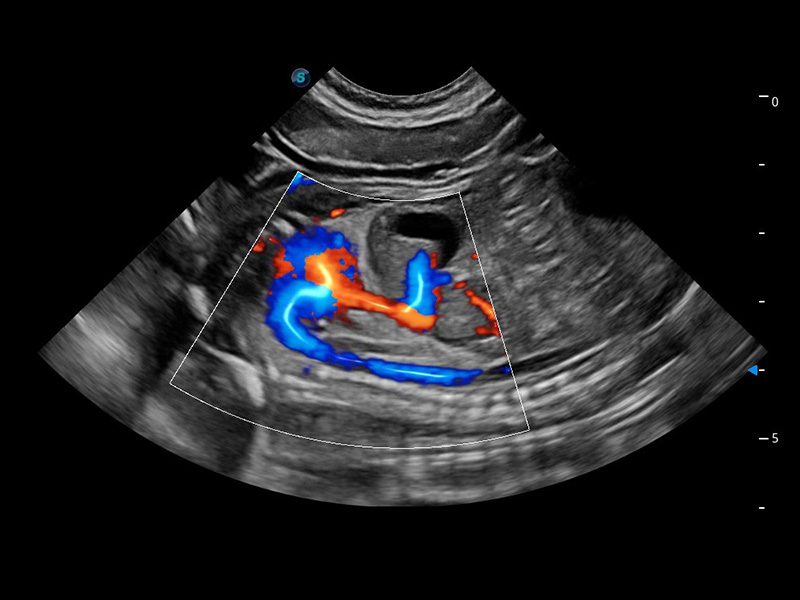

ProPet 60 作為一款高端臺式動物超聲設備,為動物醫(yī)生的日常診斷提供了一系列貼合動物臨床需求、解決臨床實際問題的高級成像功能。憑借全系列高清探頭,滿足醫(yī)生對腹部、心臟、生殖、淺表、肌骨等成像的所有需求,切實幫助您提升檢查效率,提高診斷信心。

獸用彩色多普勒超聲診斷系統(tǒng)